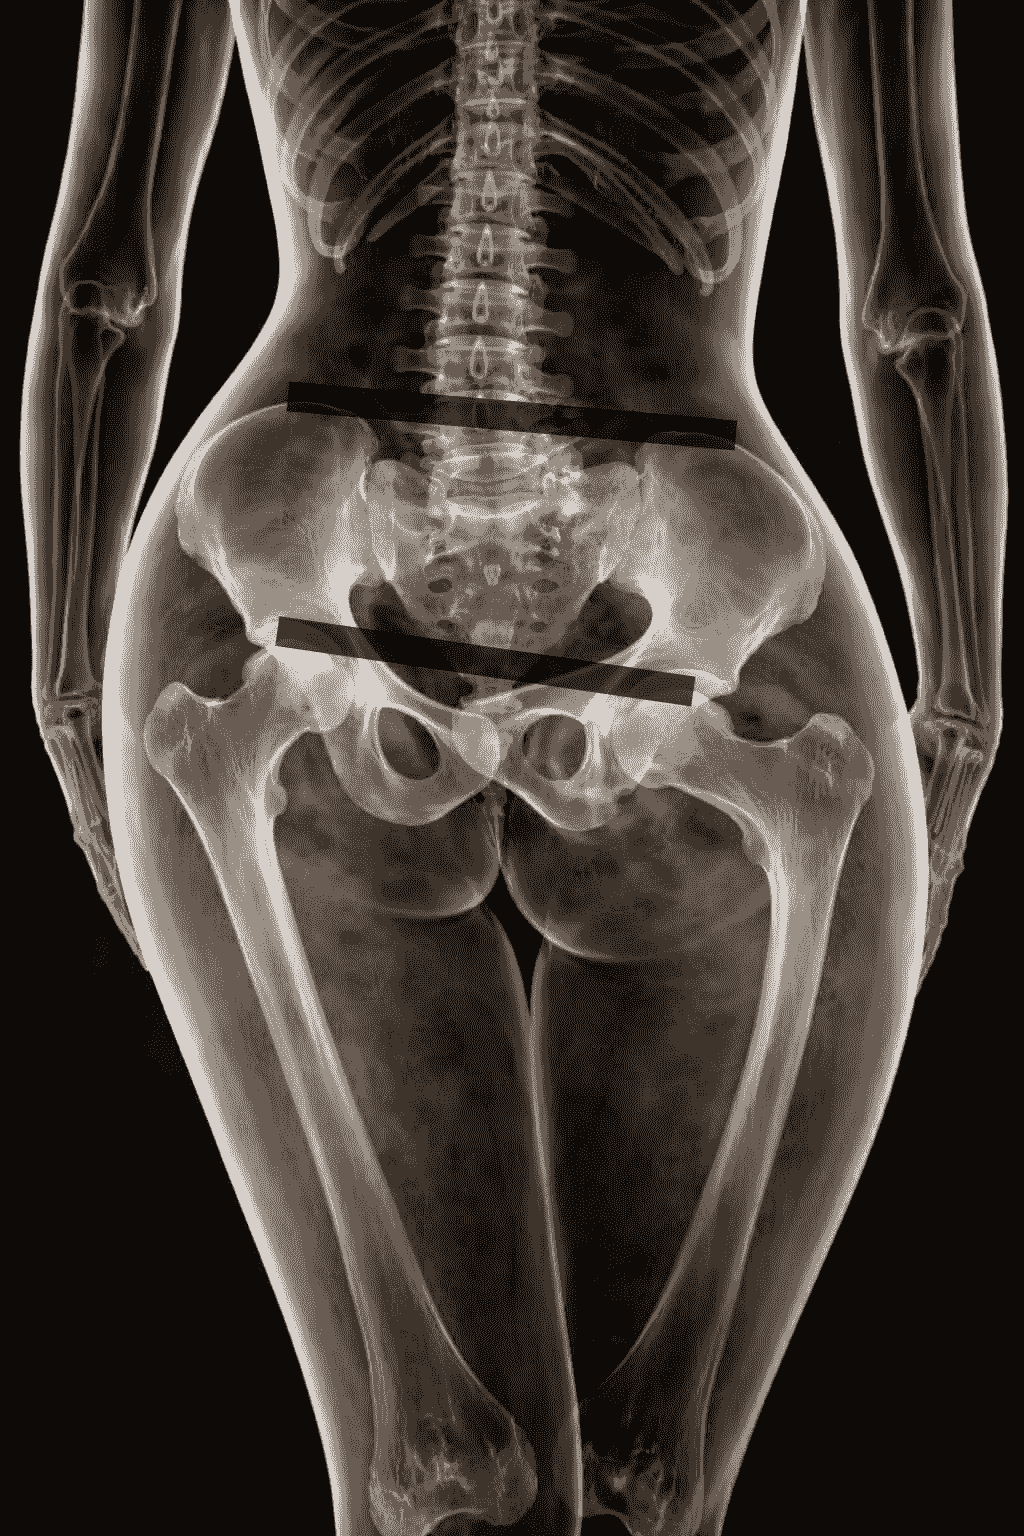

The pelvis plays a key role in spinal alignment. Due to a long-lasting incorrect pelvic position, permanent changes may develop in the lumbar, thoracic, and cervical spine. As a result, irreversible damage to intervertebral discs, facet joints, or hip and knee joints may appear, causing pain.

The pelvis is also closely related to body symmetry. It carries the entire vertebral column and has a direct connection with the lower spine and lower limbs. Because of that, any movement of the pelvis results in changes in vertebral position and affects lower-limb movement.

Scientists analyzing biomechanical disorders have noticed that incorrect alignment between spinal sections may lead to pathological conditions. The pelvis is the foundation of the spine, and its correct positioning strongly affects the maintenance of normal spinal curves. What happens in the pelvic girdle can also influence the cervical spine. Therefore, it is important to assess every spinal section, even if the patient complains.